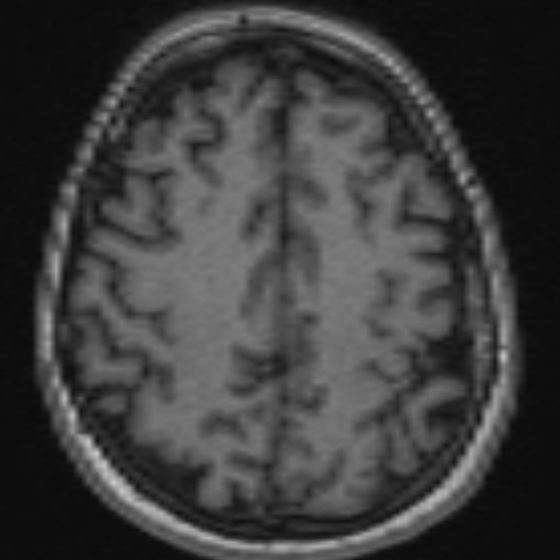

MRI: old ischaemic lesion, left post-centra gyrus

Anatomical location confirmed on fMRI